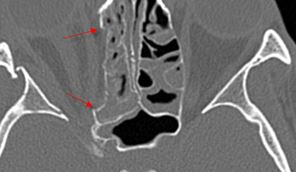

Fronto-Naso-Ethmoidal Complex

The mesial naso-orbito-ethmoid complex is fractured. Specifically, there is bony injury of the nasal bones or the frontal process of the maxilla and the medial walls of the orbit are abnormal.

There is injury of the ethmoid complex. Specifically, the ethmoid roof, olfactory fossa and the cribriform plate are fractured and/or significantly dehiscent.

The frontal bone and frontal sinus inner and outer tables are fractured.